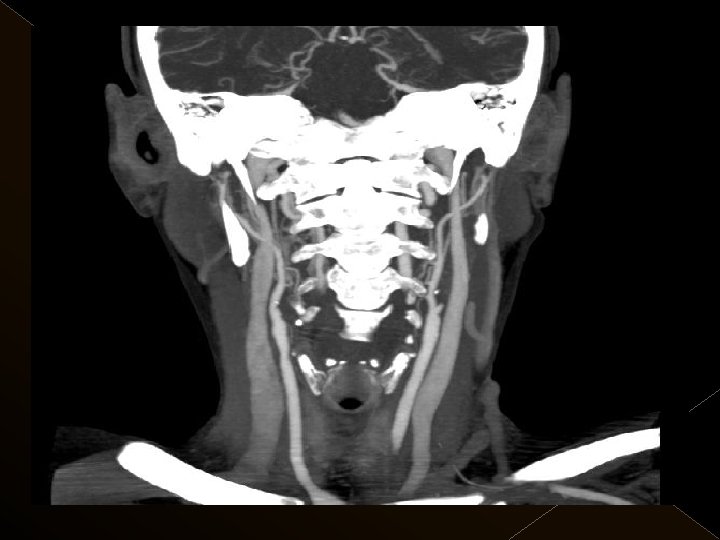

Görüntüleme İşlem öncesi § Bazal kontrastsız BT § BT anjiografi (varsa perfüzyon BT ) § MR (DW, ADC) İşlem sonrası § MR ( DW, ADC, SWI) § 24. saatte kontrol BT veya MR

� 25 hasta (16 K, 9 E) , 27 vaskuler okluzyon � 16 orta serebral arter (MCA), � 6 baziler arter ve � 5 internal karotis arter (İCA) düzeyinde olmak üzere � Toplam 25 hasta, 27 tıkanıklığa (6 sı hariç) iv tpa sonrası endovaskuler yolla müdahale edildi

KOMPLİKASYONLAR Ponksiyon bölgesi komplikasyonları � Trombektomi stentine ait komplikasyon (*1) � Diseksiyon(*2) � Karotikokavernöz fistül (‘ 1) � Hemorajik komplikasyonlar(‘ 5) Semptomatik-nonsemptomatik � İskemik komplikasyonlar (3) � Reoklüzyon (2 i. a) � Kontrast madde nefropatisi �